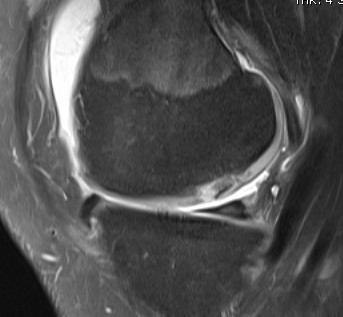

MRI Classification

Stage 1: Low signal changes, articular cartilage intact (stable)

Stage 2: Articular cartilage breached, low signal indicating fibrocartilage behind fragment (stable)

Stage 3: Articular cartilage breached, high signal indicating synovial fluid behind fragment (unstable)

Stage 4: Loose body (unstable)

Look for

- integrity of the articular cartilage

- fluid behind the lesion, suggesting instability

- displacement of the lesion

Stable

- no synovial fluid behind lesion

Unstable

- cartilage breach with synovial fluid behind lesion

Stage 1. Articular cartilage intact

Stage 2. Articular cartilage breach, but low signal intensity behind fragment

Stage 3. Articular cartilage breach and synovial fluid behind fragment (unstable)

Stage 4. Loose body

Minimally displaced loose body

Completely detached